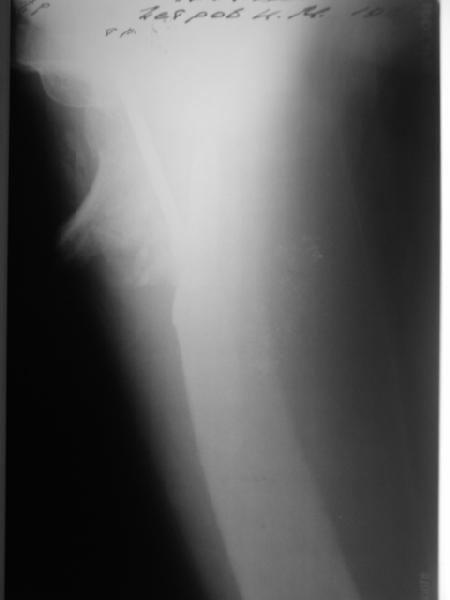

Возможно, пример (в приложении) поможет Вам определиться с выбором тактики лечения (у нашего пациента, кроме тугого ложного сустава вертельной области, сложная деформация н/3 бедренной кости; т.к. это не имеет значения к обсуждаемой теме - оставил "за кадром"). Как Вы видите, мы в данном случае не вводили чрескостные элементы в зону установки имплантата. При отказе от наложения опоры на таз (кстати, она не обязательно может быть громоздкая спицевая; арки со стержнями-шурупами, введенными в крыло подвздошной вполне достаточно) "не удивляйтесь", если опора со стержнями-шурупами, введенными в вертельной области в скором времени дестабилизируется, возникнет воспаление мягких тканей у чрескостных элементов. Такая опора "имеет на это право": нагрузка конечности от вершины дистального фрагмента до кончиков пальцев ляжет на нее. А двух-трех введенных рядом стержней-шурупов, как их не разноси от фронтальной плоскости, в данном

случае явно недостаточно для адекватной фиксации. + для того, чтобы выбрать оптимальные чрескостные элементы для промежуточной и дистальной опор, можете воспользоваться атласом

В приложении пример пациента, близкого по картине к тому, что представил Виктор (варус и смещение периферического отломка на поперечник кзади). Сделали как раз то, что Виктор исходно намеревался - аппаратная коррекция и затем гамма.